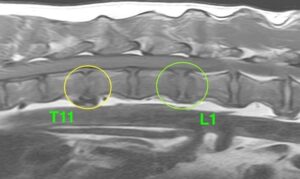

MRI検査では、胸と腰の間にある椎間板および軟骨に左の画像では周囲より白く、右の画像では周囲より黒くなっている病変を認めた(黄緑丸)

→これらの画像から胸と腰の間の椎間板脊椎炎が疑われる